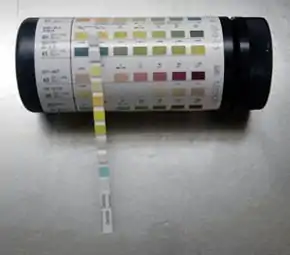

Urinalysis

Urinalysis involves assessment of the physical properties of urine, such as color and clarity; chemical analysis using a urine test strip; and microscopic examination.[3]:441 Microscopic examination is not always included: it may be reserved for samples that have abnormal results on preliminary examinations, or performed at the healthcare provider's request.[4] Test strips contain pads impregnated with chemical compounds that change color when they interact with specific elements in the urine; for example, nitrite, a compound produced by some bacteria that cause urinary tract infections, and leukocyte esterase, an enzyme found in white blood cells (WBCs) which acts as an indicator of the number of WBCs in the urine. The intensity of the color change correlates roughly with the concentration of each compound.[5]:397–406

Urine test strip

A urine test strip can quantify:

- Leukocytes – with presence in urine known as leukocyturia

- Nitrite – with presence in urine known as nitrituria

- Protein – with presence in urine known as proteinuria, albuminuria, or microalbuminuria

- Erythrocytes – with presence in urine known as hematuria

- Specific gravity

- Glucose - with presence in urine known as glucosuria

- Bilirubin - with presence in urine known as bilirubinuria

- Ketones - with presence in urine known as ketonuria

History

Helen Murray Free and her husband, Alfred Free, pioneered dry reagent urinalysis, resulting in the 1956 development of Clinistix (also known as Clinistrip), the first dip-and-read test for glucose in urine for patients with diabetes.[27] This breakthrough led to additional dip-and-read tests for proteins and other substances.[28] The invention was named a National Historic Chemical Landmark by the American Chemical Society in May 2010.[29]